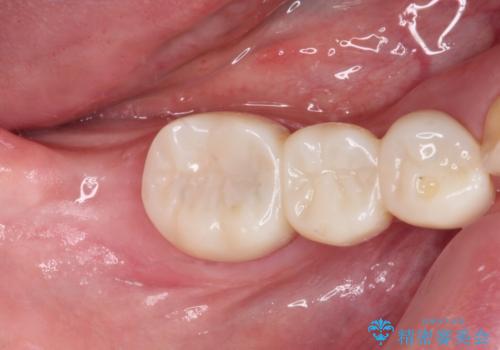

抜歯してからインプラント埋入までには時間がかかるため、その間に下顎左右臼歯の金属のブリッジをオールセラミックへ変えていくこととしました。

目立つ部分の銀歯や気になる変色歯をまとめてきれいに仕上げることができました。